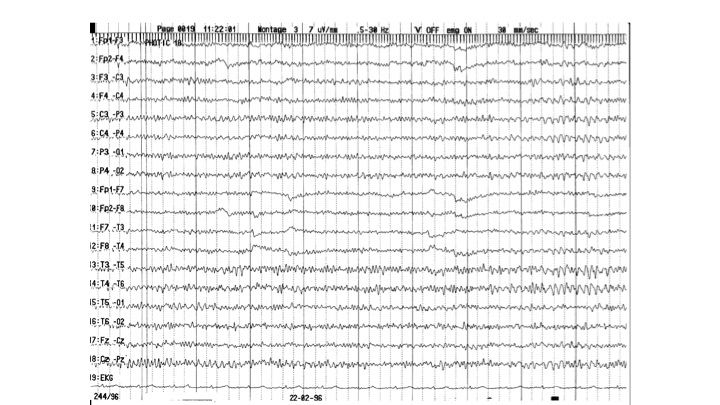

Provokationsmethoden | 36.49 zurück | weiter